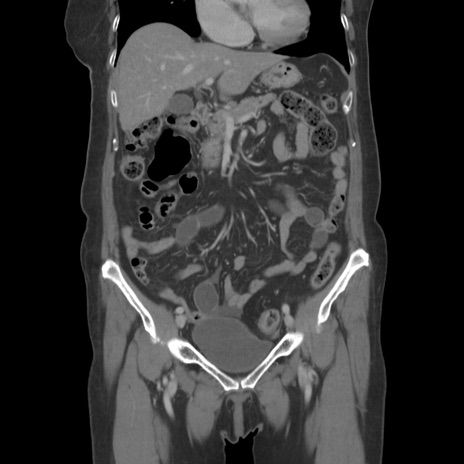

症例19(冠状断像)

【症例】80歳代女性

【主訴】下腹部痛

【現病歴】約8時間前より下腹部痛の出現あり、救急外来受診。

【既往歴】両側付属器切除

【身体所見】意識清明、下腹部正中に手術痕あり、その部位に一致して圧痛と反跳痛あり。腸蠕動音は亢進。

【データ】WBC 9300、CRP 0.15